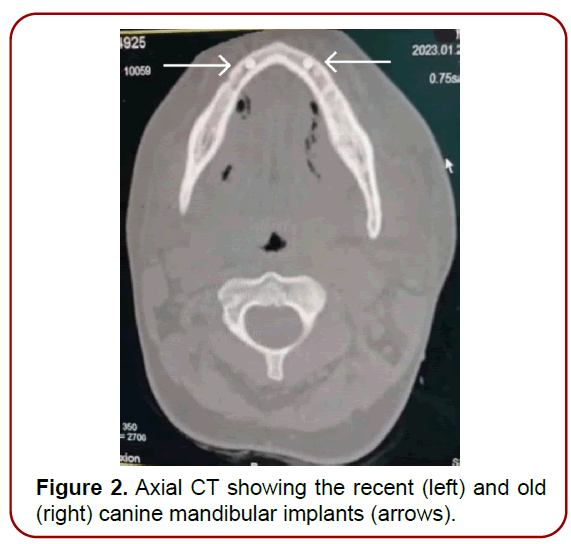

Complete blood picture showed leukocytosis. Computed tomography of the neck showed air foci in the submental, bilateral submandibular and anterior visceral neck spaces (Figure 2-4). Flexible fiberoptic assessment of the upper airway showed laryngeal edema.

Figure 2. Axial CT showing the recent (left) and old (right) canine mandibular implants (arrows).